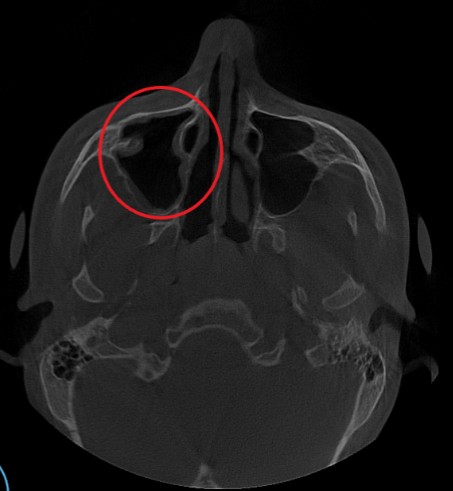

Проведена компьютерная томография околоносовых пазух, которая подтвердила наличие правостороннего гемисинусита (воспаление нескольких пазух с одной стороны), как следствие периодонтита зуба 1.6.

Представлено КЛКТ околоносовых пазух до начала лечения. Выделена зона воспаления пазух.

Ниже представлена контрольная КТ околоносовых пазух, выполненная после проведенного курса лечения. Результат совместной работы врача-оториноларинголога и врача-стоматолога.